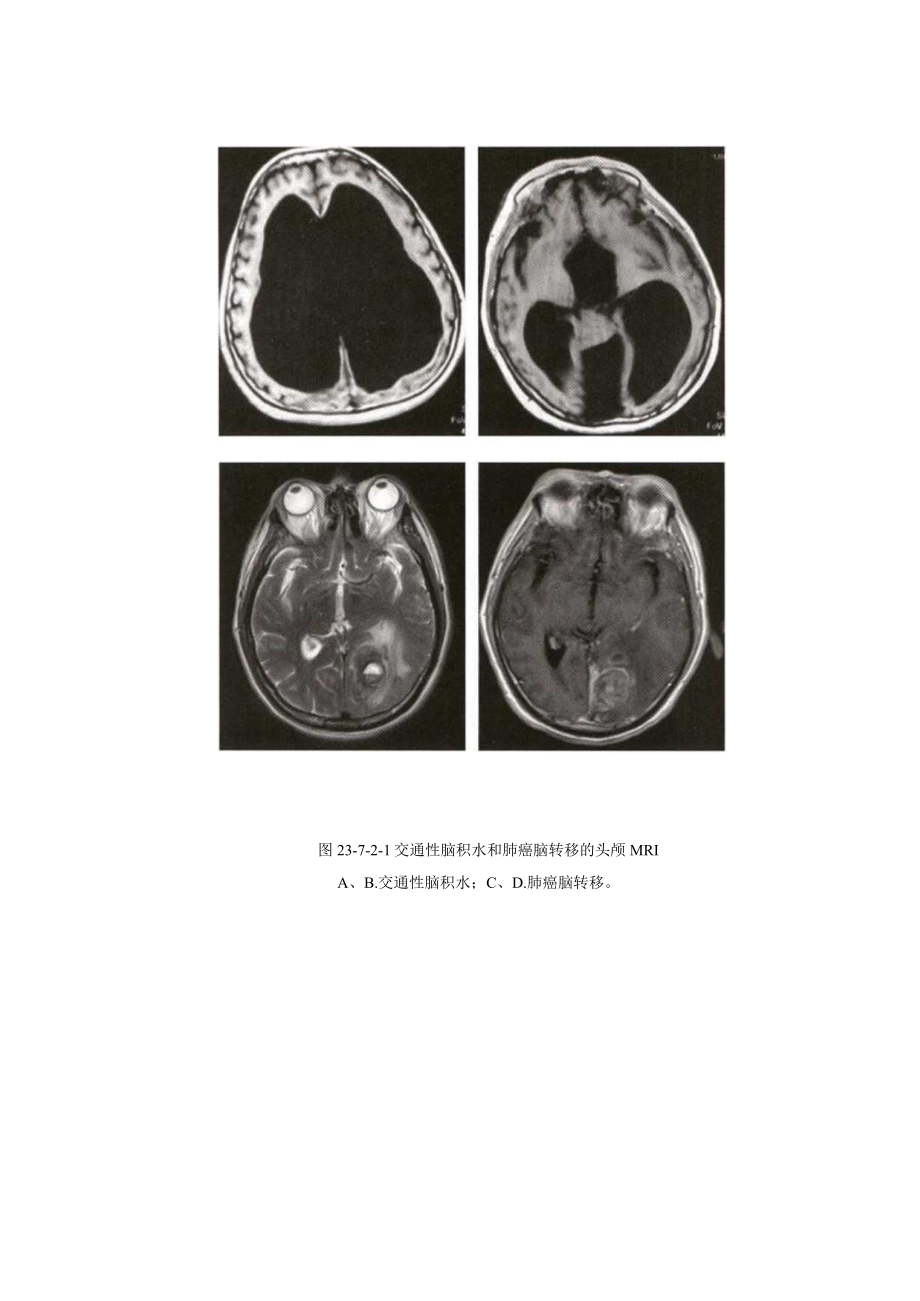

2、但病程往往进展迅速。大多数患者有中枢神经系统功能紊乱的症状,大约50%的患者有头痛症状,以及常见的恶心、呕吐、语言障碍、肢体肌力减退、共济失调、脑神经麻痹等;25%的患者出现视乳头水肿。发病部位以大脑中动脉供血区等血运较丰富区域为主,占一半以上,而且容易发生在灰质和白质交界处,以额、颖、顶叶多见,枕叶少见。颅内转移瘤70%80%是多发的,大部分转移瘤造影剂增强明显,可以表现为一致增强,如果转移瘤超过血管供应也可表现为环状增强(图23-7-2-1)。转移瘤通常致血管源性水肿,且常会和肿瘤大小不成比例。根据病变部位不同可出现局限性定位体征,如偏瘫、偏身感觉障碍、失语、眼震、共济失调等体征。原发肿瘤

3、向颅内转移的途径:经动脉血行转移;经淋巴系统转移;经蛛网膜下腔转移;经静脉转移。【治疗】1 .手术治疗单发性转移瘤,原发灶已切除或暂时尚未找到原发灶,且能耐受手术者:多发性病灶,较大者已引起明显颅内高压威胁患者生命者。2 .放疗、丫刀、X刀治疗、射波刀等放射治疗适合于单发或多发转移瘤,其疗效与手术治疗相仿。原发灶不能切除以及病灶超过3个者疗效差。图23-7-2-1交通性脑积水和肺癌脑转移的头颅MRIA、B.交通性脑积水;C、D.肺癌脑转移。3 .化疗根据原发灶的病理性质选用化疗药物。二脑膜癌病脑膜癌病(meningea1.carcinomatosis,MC)是指恶性肿瘤弥漫性或多灶性软脑膜播散